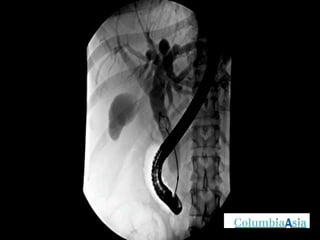

ERCP (Endoscopic Retrograde Cholangio Pancreatography) is an endoscopic procedure used to diagnose and treat issues in the bile and pancreatic ducts. It involves positioning an endoscope and using x-rays to view the ducts while performing procedures like draining bile ducts, removing gallstones, and placing stents. Potential complications include pancreatitis, bleeding, infection, or perforation. Careful pre- and post-procedure steps like monitoring and antibiotics are important to minimize risks.